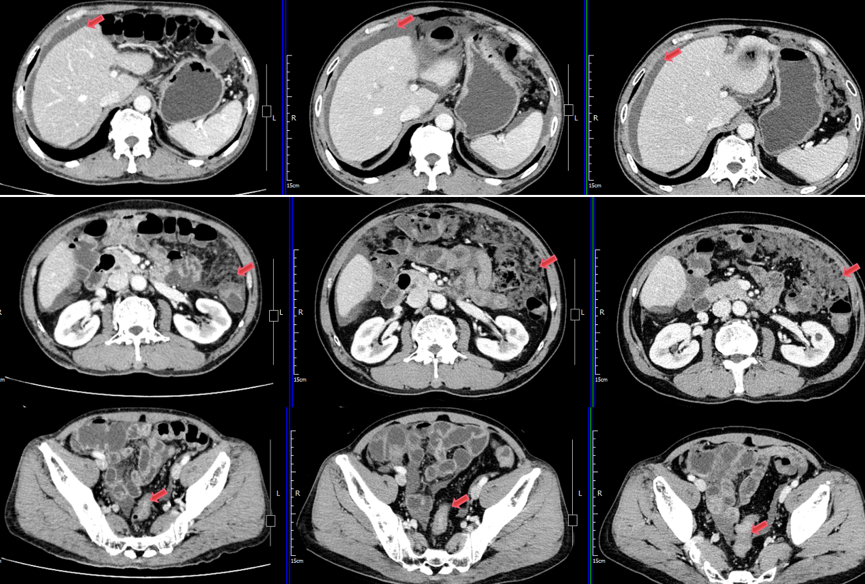

8.png

图8. 患者后续复查影像对比  疗效SD